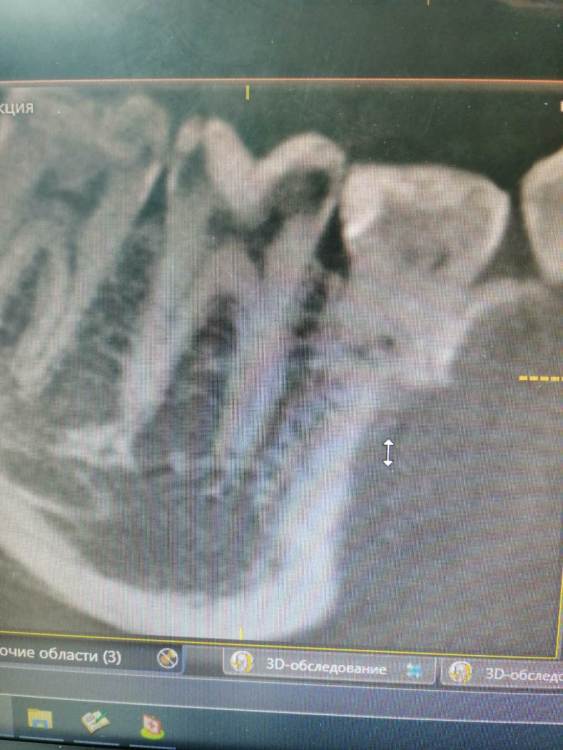

Тильда Опубликовано 30 апреля, 2021 Поделиться Опубликовано 30 апреля, 2021 (изменено) Коллеги, очень нужен ваш совет. В октябре 2020 года проведено эндо лечение 4.6 по диагноз пульпит хронический. Лечение было проведено в одно посещение, ирригант - гипохлорит, M-Two до 30 медиальные и до 40 дистальный, вертикальная конденсация. Недавно (через пол года после лечения) пациентка обратилась снова с жалобами на боли в области пролеченного ранее зуба. Причём причинный зуб локализует чётко. Боли появились сразу после лечения, постепенно немного стихли, но полностью не болит. Болит при механическом раздражение вестибулярной стенки, по словам пациентки отдаёт по челюсти. Перкуссия и термо проба безболезеннные. Слизистая без особенностей. На одном из срезов КТ можно заподозрить расширение периодонтальной щели в периапикальной области медиальных корне, но вроде бы и до лечения картина похожая. Есть ли смысл сделать повторное эндо? Буду благодарна за ваши мысли по поводу дальнейшей тактики. Извиняюсь за качество снимков и понимаю, что их сложно оценить Изменено 30 апреля, 2021 пользователем Тильда Ссылка на комментарий